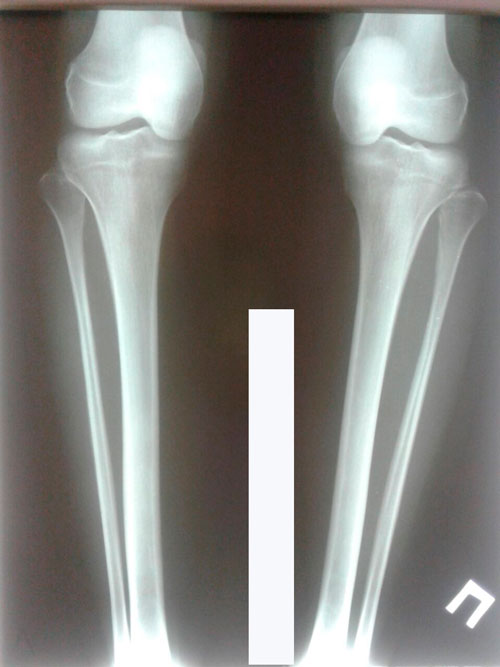

Ровные и красивые!

Re: Ровные и красивые!

Дата операции 06.02.2018г.

Дата снтия аппаратов 02.05.2018г.

Срок лечения 86 дней.

Как мастерски исправлена такая страшная Ротация!